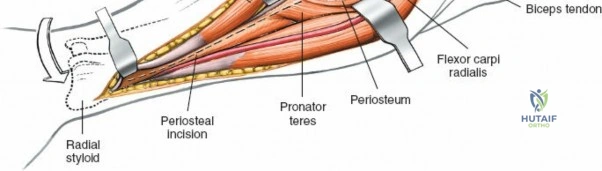

Accurate identification of surface landmarks is the first step in a successful Henry approach. Palpate the biceps tendon, a stout, taut structure crossing the anterior elbow joint just medial to the brachioradialis muscle. Next, palpate the brachioradialis itself, the fleshy muscle forming the lateral border of the cubital fossa. Finally, identify the styloid process of the radius distally. Note that when the forearm is fully supinated (the anatomic position), the radial styloid is truly lateral.

Make a straight or gently curved incision beginning at the anterior flexor crease of the elbow, just lateral to the biceps tendon. Extend this incision distally toward the styloid process of the radius. The exact length and placement of the incision are dictated by the specific pathology; the approach is highly modular, and often only the proximal, middle, or distal third of the incision is required.

Exposing the proximal third of the radius requires extreme vigilance due to the proximity of the posterior interosseous nerve. The key anatomical landmark here is the insertion of the biceps tendon. Follow the biceps tendon distally to its insertion on the bicipital tuberosity of the radius. A small bursa lies just lateral to the tendon; incise this bursa to gain initial access to the proximal radial shaft. Because the radial artery lies superficial and medial to the tendon at this level, all deep dissection must remain strictly lateral to the biceps tendon.

The proximal radius is draped by the supinator muscle. The PIN passes directly through the belly of the supinator. To protect the nerve, the forearm must be fully supinated. Supination dynamically rotates the radius, carrying the insertion of the supinator anteriorly and simultaneously displacing the PIN laterally and posteriorly, safely away from the surgical field.

With the forearm fully supinated, identify the broad insertion of the supinator on the anterior aspect of the radius. Incise the supinator directly along the line of its insertion onto the bone. It is critical to detach the muscle by dividing its insertion sharply at the bone, rather than splitting the muscle belly, which would risk cutting the PIN.

Proceed with strict subperiosteal dissection, elevating the supinator laterally off the bone. This is one of the rare instances in orthopedic surgery where the safety gained by staying in a subperiosteal plane completely outweighs the theoretical vascular damage to the bone caused by periosteal stripping. The elevated supinator muscle belly now acts as a protective cushion for the PIN.